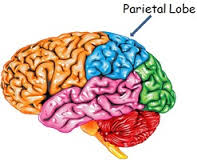

Parietal lobes

The parietal lobes are responsible for complex behaviors, including all behavior involving the senses. They are also involved in body positioning and movement; sensory perception; sensory neglect; language comprehension; constructional ability; right-left differentiation; self-awareness; and the ability to perform mathematical calculation.